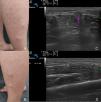

The first case is a 34-year-old man with no relevant past medical history, who presented with lumps on the sides of the legs. The lesions had appeared 7 years earlier and had increased in number and size. They were not associated with injuries. The patient reported stabbing pain after walking for long periods. Physical examination revealed several soft nodules that could be compressed on palpation; the nodules were more evident when the patient was standing or on resisted dorsiflexion of the foot in the supine decubitus position (Figs. 1A and B). The ultrasound examination was performed using a variable-frequency (8-18MHz) linear probe connected to a MyLab Class C device (Esaote) in B-mode, with the patient in the standing and supine decubitus position. When the patient was standing, B-mode ultrasound showed a partial protrusion of the tibialis anterior through a defect in the muscle fascia; the protrusion disappeared when the patient was in the supine decubitus position (Figs. 1C and D). The patient was advised to use compression measures and to return if the protrusion grew or he suffered discomfort.

A, Nodules on the side of the right leg. B, Nodules on the side of the left leg. C, B-mode ultrasonography: protrusion of the muscle during contraction, through the defect in the fascia (arrow). D, B-mode ultrasonography: discontinuity of the fascia during muscle relaxation (between markers).